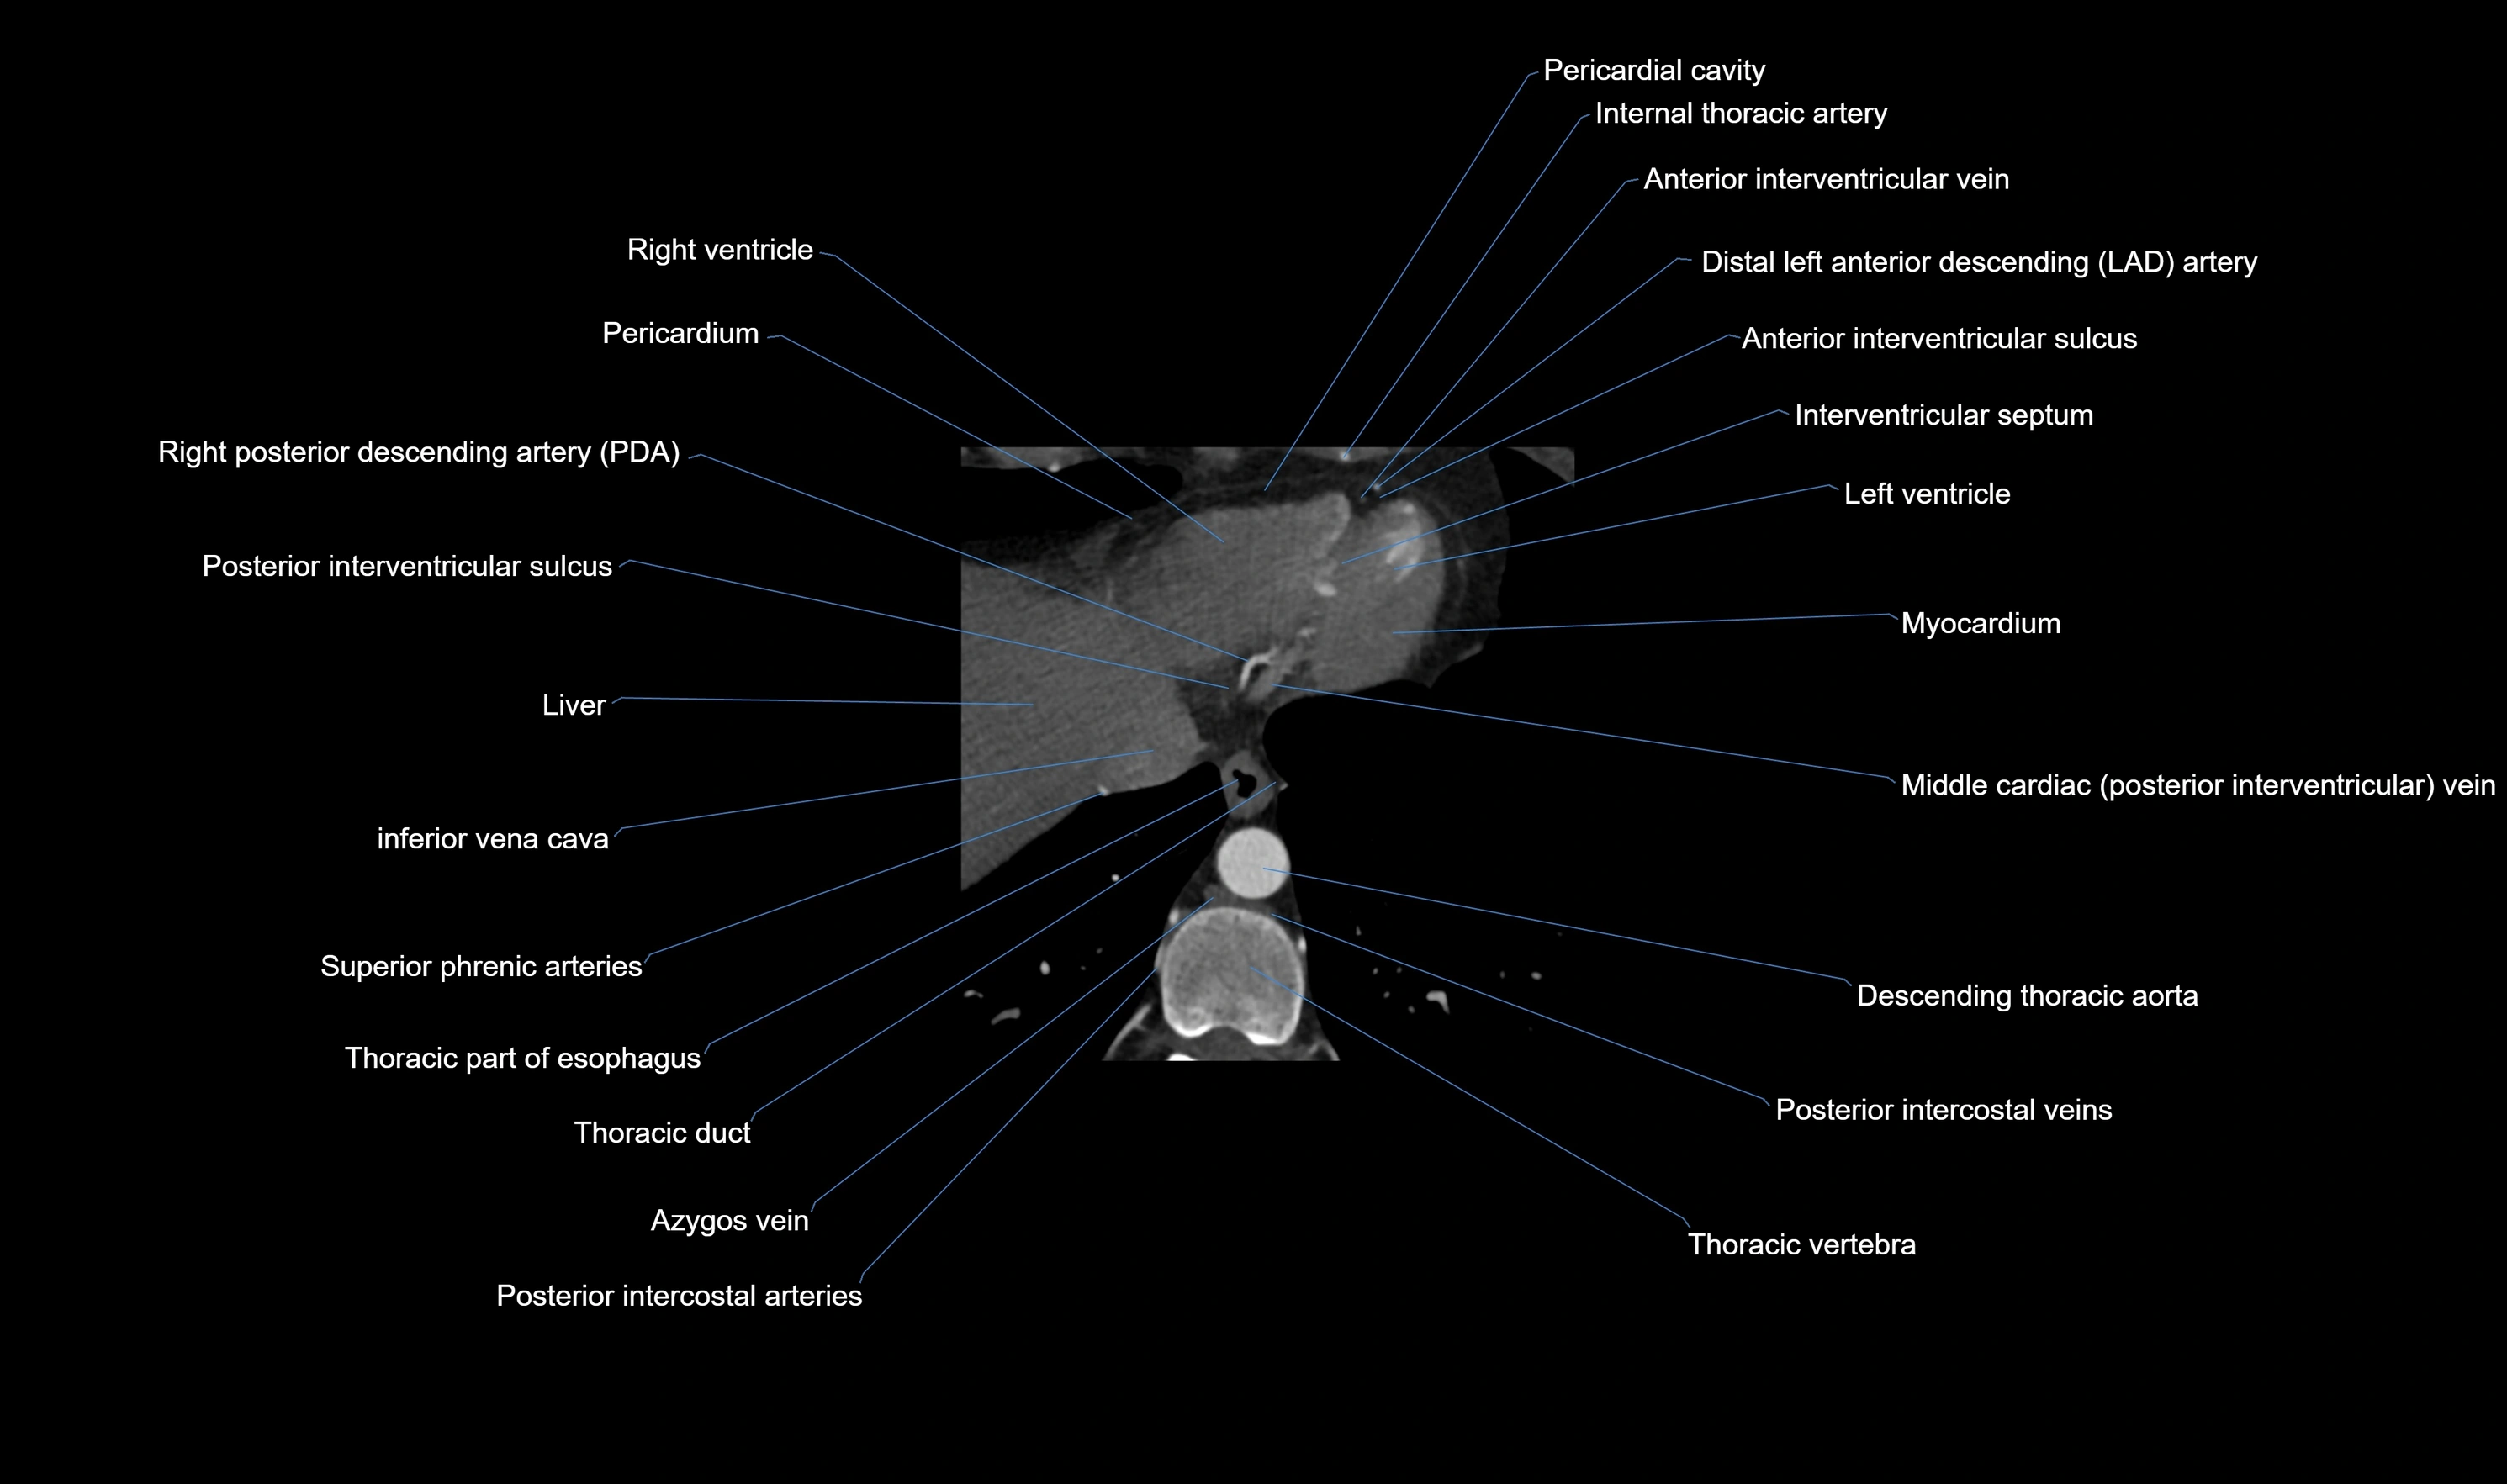

CT images